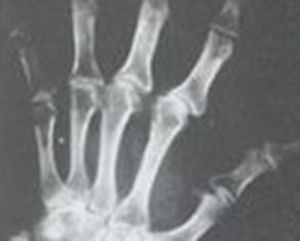

本病主要累及軟骨內成骨的骨骼,特別是四肢骨,表現為透明軟骨的變性壞死及伴隨的吸收、修復性變化。軟骨細胞常見凝固性壞死細胞核固縮、碎裂、溶解消失後,殘留紅染的細胞影子。進而殘影消失基質紅染,成為灶狀、帶狀的無細胞區。壞死區還可進一步崩解、液化。壞死灶周圍存活的軟骨細胞常有反應性增生,形成大小不等的軟骨細胞團(圖6)在鄰近骨組織處壞死部位可發生病理性鈣化;初級骨髓的血管和結締組織侵入壞死灶內,出現機化、骨化,最終為骨組織軟骨壞死以累及成熟中的軟骨細胞(肥大軟骨細胞)為主,呈現近骨性分布。壞死擴大時也會波及其他層次的軟骨細胞。壞死灶常為多發性,大小不一呈點狀、片狀或帶狀。

當壞死灶貫穿整個骺板時,由骺核和乾骺端兩個方向進行壞死物的吸收機化和骨化,終於導致骺板提前骨性閉合,該管狀骨的縱向生長早期停止,造成短指(趾)或短肢畸形。

根據病區接觸史、症狀和體徵以及手骨X線拍片所見手指腕關節骨關節面、乾骺端臨時鈣化帶和骺核的多發性對稱性凹陷、硬化、破壞及變形等改變可診斷本病。X線指骨遠端多發對稱改變為本病特徵性指征。

5.關節增粗短指(趾)畸形是本病晚期的X線徵象因伴有繼發性骨關節病可發生關節變形。

X線診斷本病的影像學特點:X線診斷本病以手、腕片為主,必要時加拍踝關節側位及足正位片。指骨幹骺端的改變發生較早,變化較快,但有些輕微的改變不僅可見於本病,也可見於非病區健康兒童或其他骨病。指骨遠端為無骺核骨端,由於解剖生理所決定,本病的骨端損害X線顯影較晚發展緩慢但在診斷上更具有意義。特別是病變早期,在患者尚無明顯臨床症狀時,可先有指骨病變的X線表現。通常先攝手部X線片以手部乾骺端改變作為X線早期診斷的依據。必要時可加攝踝關節側位及足正位片1982年制定的大骨節病X線診斷標準如下:

(1)掌指骨:

①乾骺端:a.乾骺端先期鈣化帶出現小凹陷或鈣化帶中斷伴有局部骨小梁結構紊亂;b.先期鈣化帶部位硬化增寬、不整;c.乾骺端各種形態的凹陷伴硬化;d.有凹陷骺側先期鈣化帶出現(不包括小指中節和拇指近節)。

②骨端:a.骨性關節面模糊變薄、中斷、毛糙不整,呈鋸齒樣改變;b.骨性關節面平直、凹陷硬化;c.骨端邊緣缺損或附近出現鈣化骨化灶;d.骨端變形關節緣骨質增生,骨小梁結構紊亂,囊樣變。

③骨骺:a.骨骺關節面模糊、凹陷鈣化;b.骺核與乾骺端明顯或局部接近;c.骺線局限性過早融合或局部硬化;d.骺核邊緣模糊、中斷不整或凹陷硬化;e.骺核形態異常、破壞殘留消失或再現。